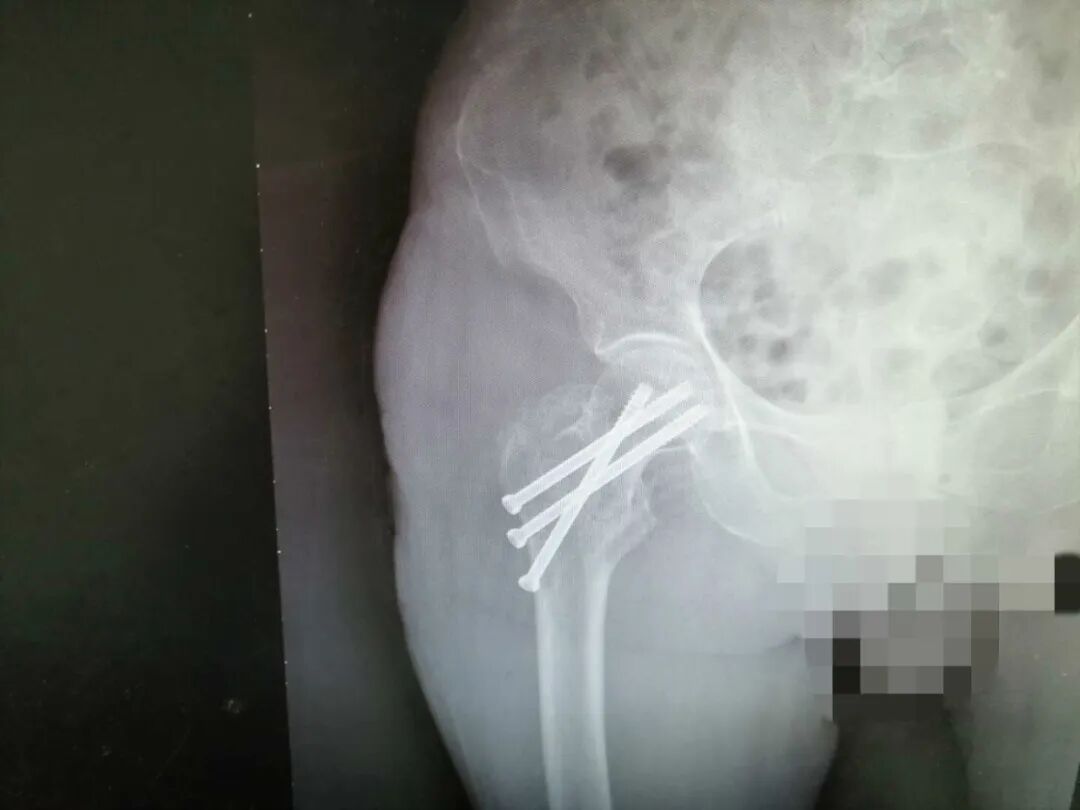

3月28日当天,手术如期进行,早上,医生查完房,护士测量了患者生命体征、评估了患者身体状况后,张奶奶在家属陪同下准时送入手术室,于此同时,我们的护理人员在做术后护理准备工作。因为是手术患者,加上要长期卧床,我们一般都会更换床单,保持整洁,保证了患者卧床期间有个良好的舒适感,也可以降低感染和褥疮发生的风险,并在其床头放置好心电监测仪和备好吸氧等测量生命体征的用品,以备不时之需。两个小时过去了,手术顺利完成,张奶奶被送回病房进行后续康复治疗,护士加强了护理措施,防压疮、防跌倒、防坠床。